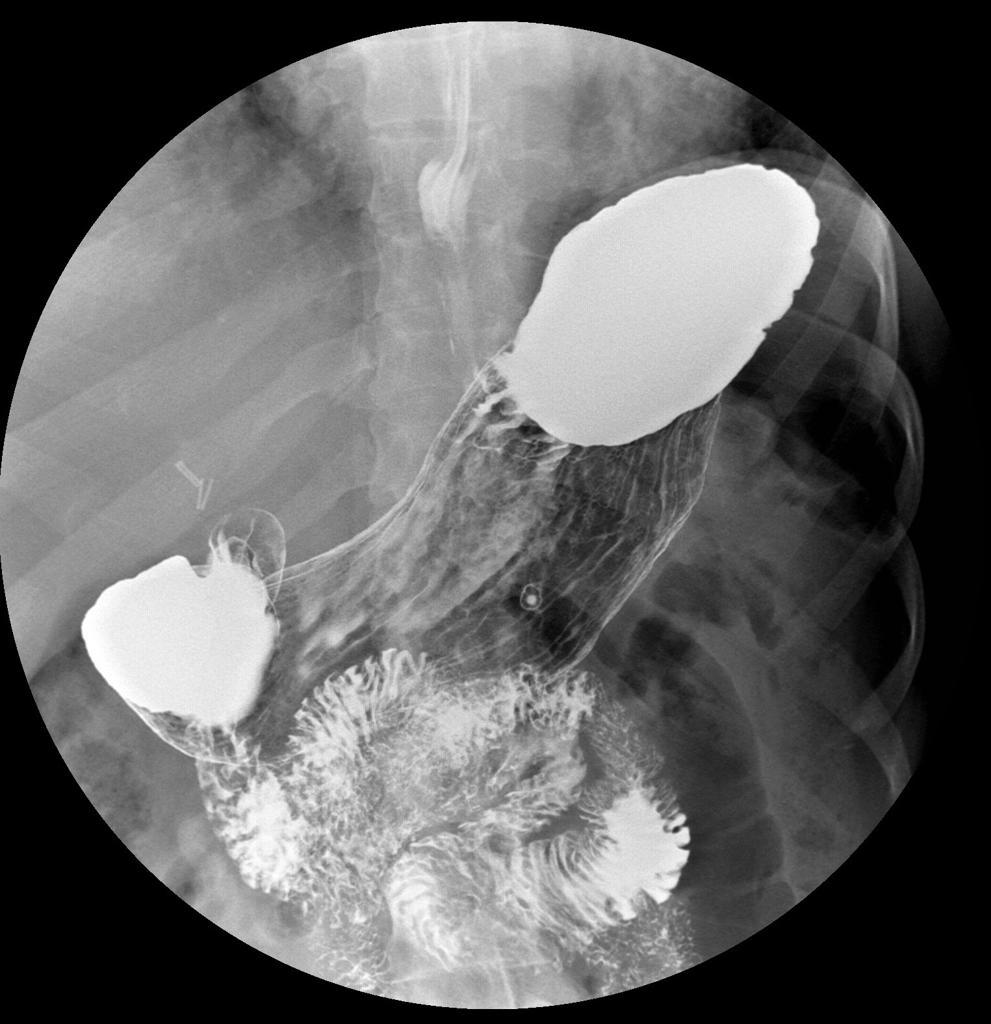

Menetrier’s disease

Classic appearance with massively enlarged folds in the body without abnormality in the antrum.

This condition is characterised by hypertrophy of gastric glands, achlorhydria and hypoproteinaemia. Loss of protein from the hyperplastic mucosa into the gastric lumen results in a protein-losing enteropathy, and may produce disabling symptoms. The disease is characterised by markedly enlarged, often bizarre gastric folds most prominent in the proximal stomach and along the greater curvature.